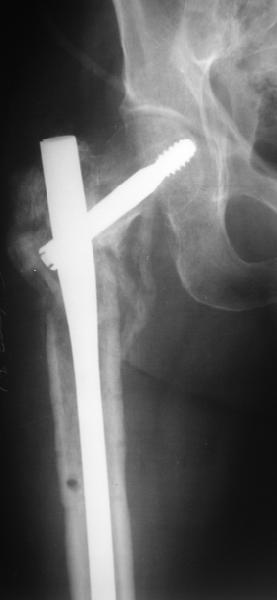

Уважаемые коллеги! Нужен совет.Больной Х., 21 год, ДЗ: ложный сустав вертельной области правого бедра.

Травма 8 мес. назад, ДТП, получил закрытый межвертельный перелом правого бедра. Лечился в городской больнице одного из городов-спутников г. Караганды скелетным вытяжением в течение 3 недель, затем кокситной гипсовой повязкой 2 мес. В настоящее время имеется укорочение конечности на 7 см, умеренная боль в вертельной области; ходит без костылей, полностью нагружая больную конечность, при нагрузке отмечается смещение дистального отломка проксимально примерно на 1,0 см.; объем движений в коленном суставе сохранен; при пальпации отломков боли нет, умеренная патологическая подвижность. Планируем внеочаговый остеосинтез спице-стержневым аппаратом, дистракция до восстановления длины бедра, вторым этапом остеосинтез стержнем Гамма. Есть надежда, что на дистракции пойдет сращение и у больного хватит терпения завершить лечение в аппарате.

В приложении пример пациента, близкого по картине к тому, что представил Виктор (варус и смещение периферического отломка на поперечник кзади). Сделали как раз то, что Виктор исходно намеревался - аппаратная коррекция и затем гамма.